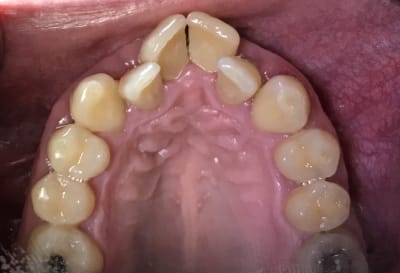

En attendant que le nouveau réponde ... Dans un style différent : 38 ans . très complexé. Aucun dentiste n’a voulu le toucher (pour le secteur antérieur) . Je lui ai dit qu’il fallait lui déglinguer la mâchoire. Sauf qu’il ne veut pas faire de chirurgie orthognatique, c’est sa seule condition . Par contre est prêt à mettre n’importe quel prix pour retrouver un beau sourire. N’est ni fermé à l’ortho , ni fermé à l’implantologie.

à condition de maitriser l'hygiene avant tout et de preserver les canines à tout prix

et à condition que l'occlusion soit bien tolérée examen soigneux des ATM et des muscles masticateurs

la seule solution esthétique pour ne pas lui faire des contrales de lapin passe par une fausse gencive

Le cas du début c'est avant tout une supraclusie carabinée.

Faut voir si il serre les dents, comment il respire et deglutit....

Comme ça tu peux remonter en postérieur et te donner une chance de réhabiliter devant.

Si et seulement si il supporte alors restaurations résine en postérieur et devant ensuite.